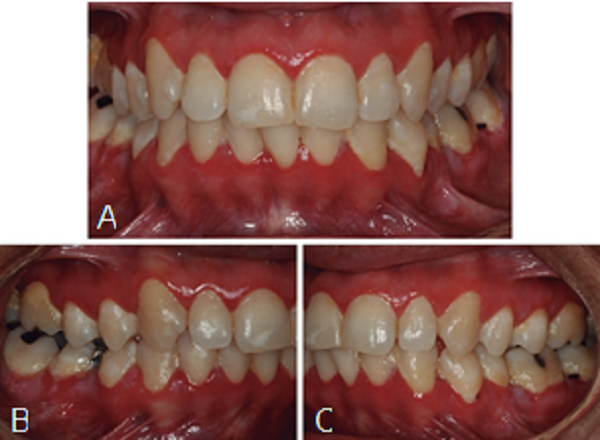

Al realizar el examen clínico, se observó áreas erosivas en margen gingival superior e inferior, en zona posterior inferior por vestibular se observaron lesiones pseudomembranosas descamativas, abundante placa bacteriana en molares (Figura 1), paciente refiere que le arde mucho al cepillarse, que las lesiones aparecieron hace seis meses y medio en forma espontánea. No presenta bolsas periodontales. Resto de los tejidos dentro de límites normales. No se palparon adenopatías, ni se observaron alteraciones de contorno facial ni en piel, pero refiere que hace dos meses le apareció una única úlcera en espalda que fue tratada con prednisona en crema y le sanó.

Luego de una semana de tratamiento tópico las lesiones disminuyeron notablemente de tamaño; además, la sintomatología desapareció completamente, lo cual permitió que se higienizara correctamente. Se realizó seguimiento por ocho años, en los dos primeros años a pesar que tenía un buen control de placa bacteriana mantenía una leve descamación gingival, que luego del divorcio desapareció por completo y la paciente lo asoció al estrés que le ocasionaba su exesposo.

Actualmente refiere funcionalidad bucal y confort, mantiene los controles con los diferentes especialistas. A nivel bucal ha estado muy estable y no ha presentado áreas erosivas o descamativas (Figura 3), sin problema se le han podido realizar cirugías de las terceras molares inferiores con osteotomía y odontosección sin complicaciones, una endodoncia en el primer molar inferior izquierdo, debido a la estabilidad periodontal se le realizó un alargamiento coronario en distal de dicha molar, con gingivectomía y osteotomía, obteniendo una adecuada cicatrización de los tejidos periodontales. En ningún caso se presentó reactivación del PV. La paciente se encuentra con un intervalo de mantenimiento periodontal cada 6 meses, donde se han controlado los factores locales de retención de placa bacteriana, para su estabilidad en el tiempo. En piel cuando ha tenido alguna lesión le ha resuelto fácilmente con tratamiento tópico enviado por el dermatólogo.